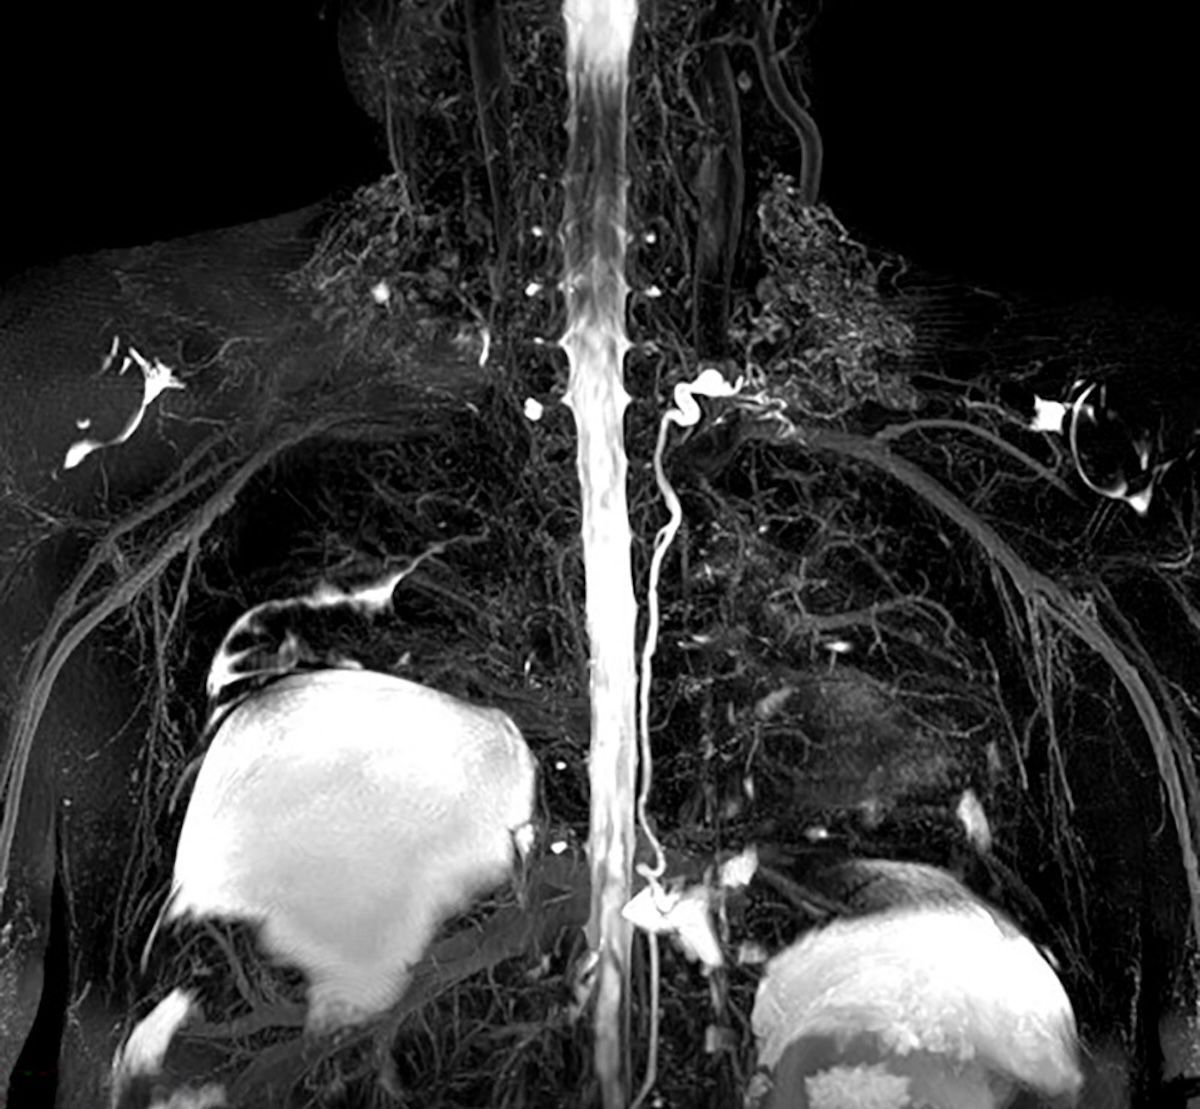

Double orifice mitral valve #Cardiotwitter #whyCMR #JACCcaseReports @AlohaMeaveMD @VDelgadoGarcia @JGrapsa